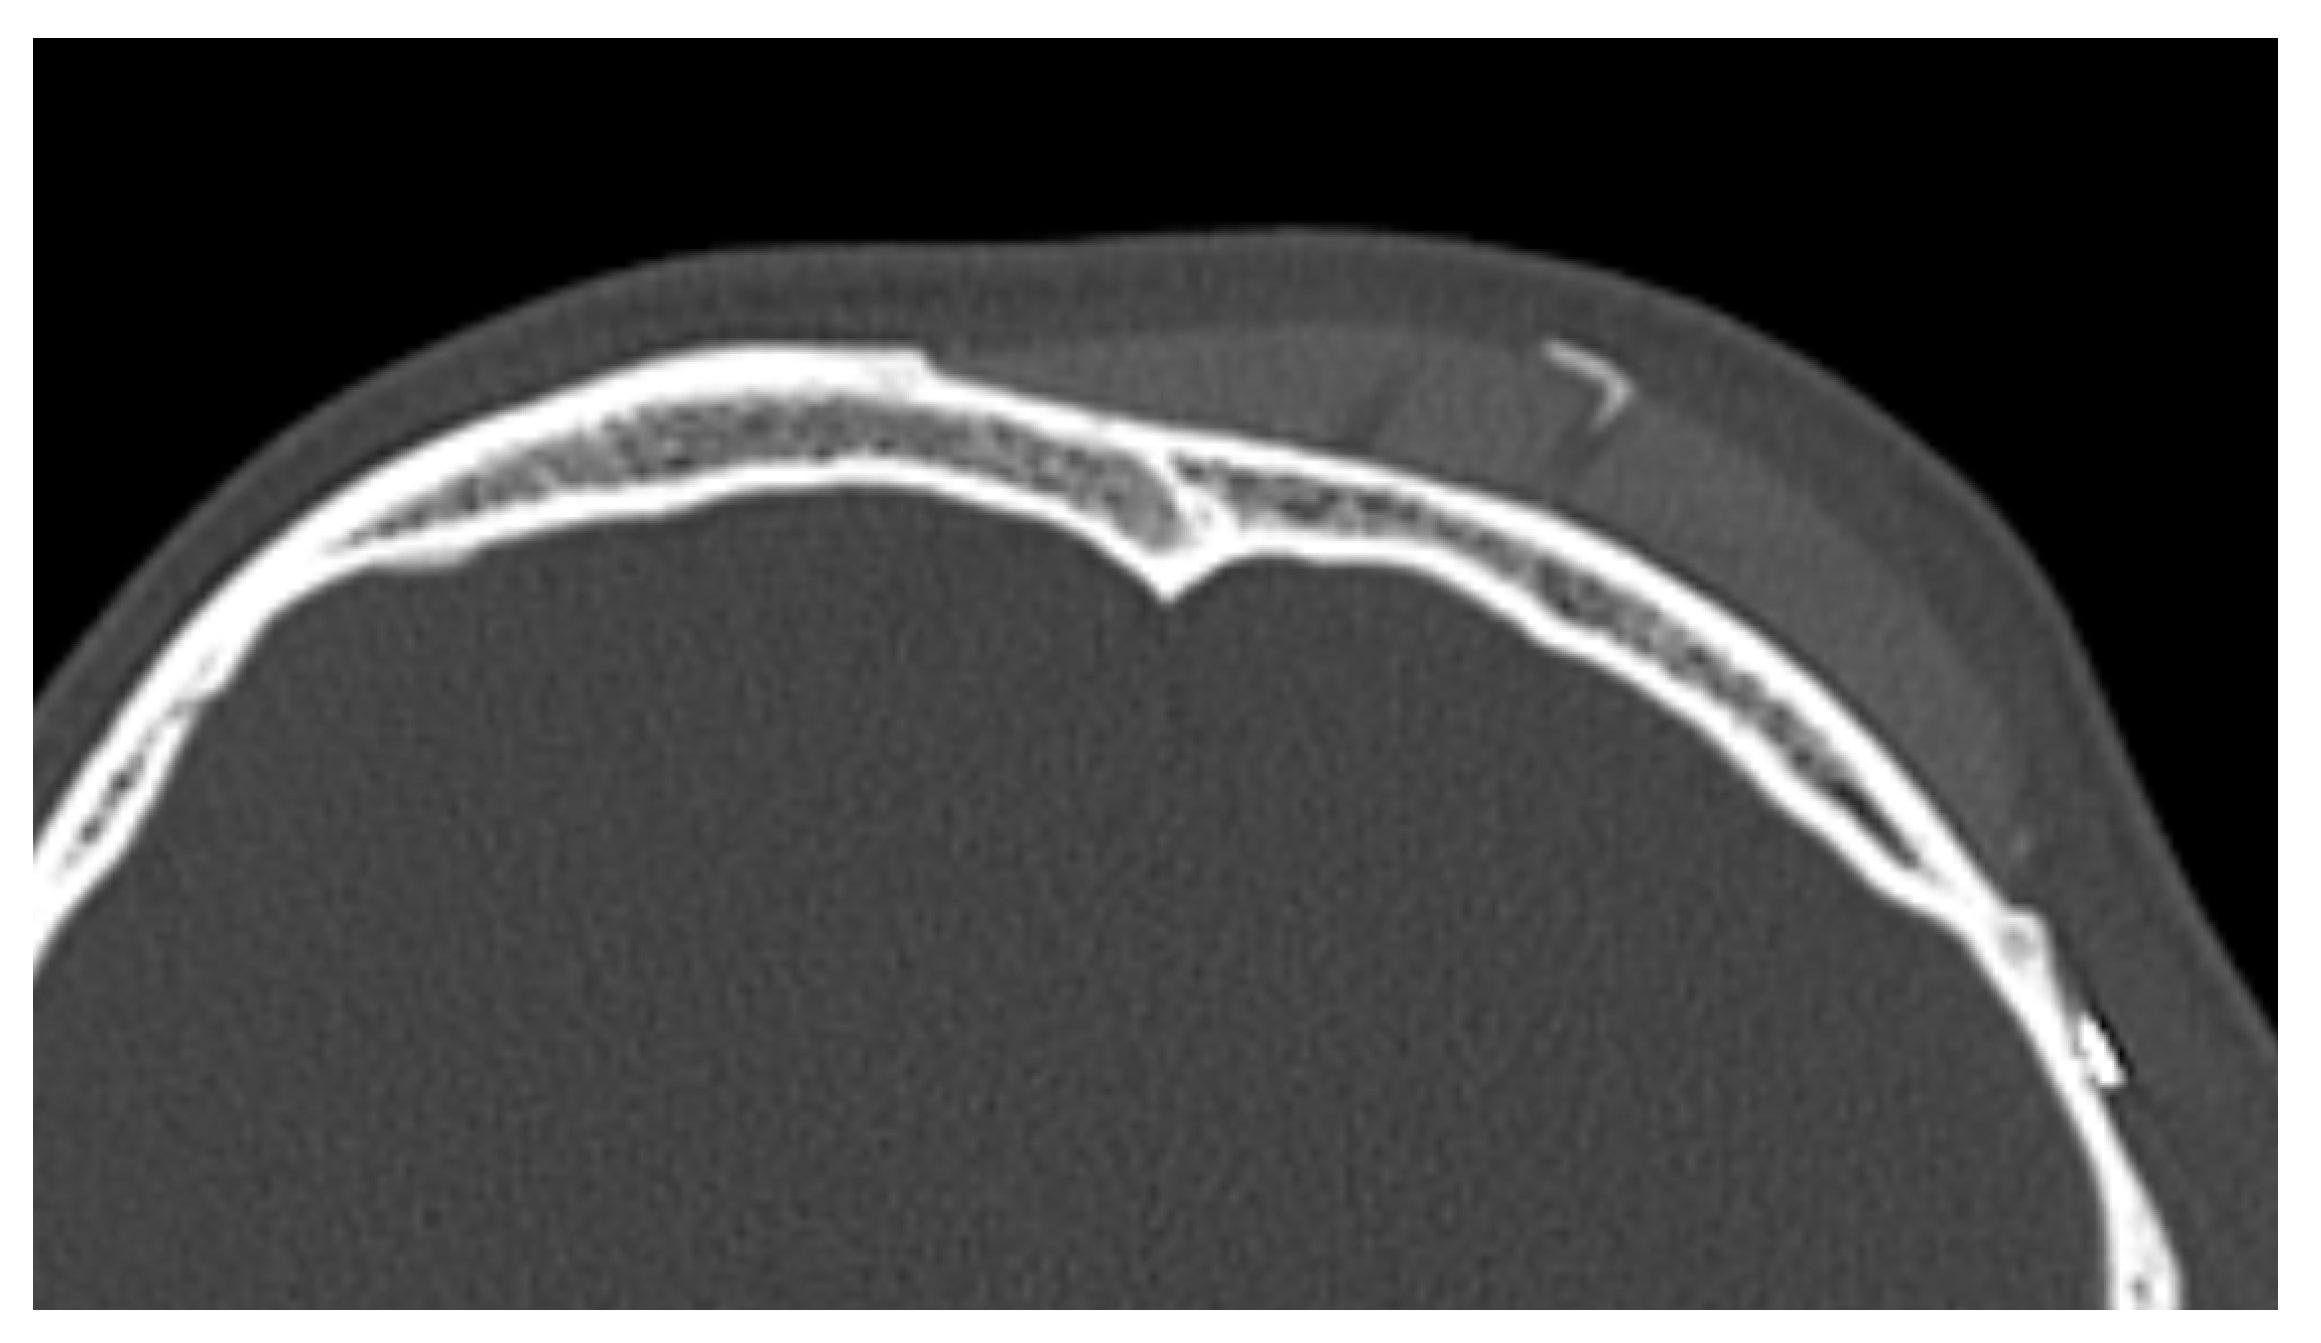

In 9 out of 10 CT scans, radiological evidence of bone regrowth on the surface and edges of the implant was not evident. In one case, at 6 and 12 months, a bone regrowth consisting of islands of skull regeneration beneath the PEEK implant at the bone–implant interface was documented. This was the case of a 34-year-old female patient with a history of head injury who underwent autologous bone flap removal for infection along with wound dehiscence and secondary implant of PEEK defective cranioplasty. A retrospective analysis of the radiological exams revealed periosteal residual “spots” in the context of the defect, frontally. After PEEK cranioplasty, these spots expanded and fused to form a flake “regeneration front” of 25 mm length and 2.3 mm maximum thickness starting from the PEEK–frontal bone interface [see Figure 1].

Figure 1.

Bone formation in factory created holes of PEEK prosthesis.